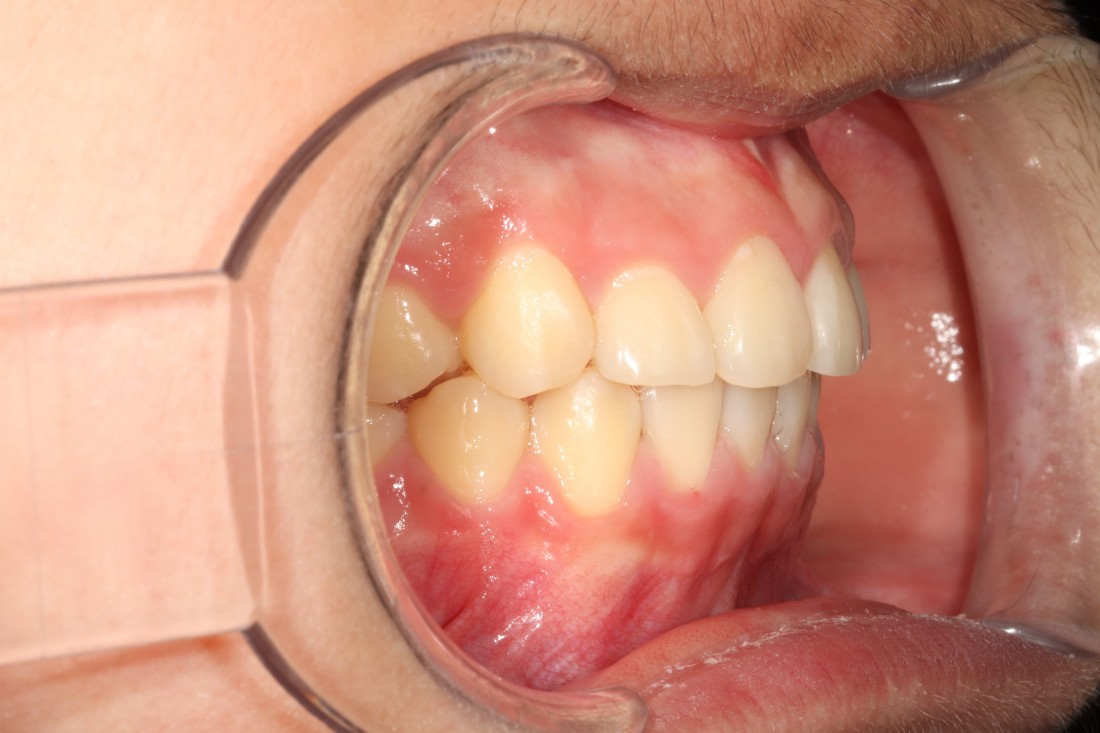

![]() | ![]() |

광주 덧니교정 치과는

대표원장인 제가 직접

다양한 교정 전/후 케이스를

공유하고 있습니다.

다양한 각도에서 촬영한

교정 전/후 사진을 직접 확인할 수 있어

광주 덧니교정 치과의

실력있는 진료를 증명하고 있습니다.

발치를 진행한 덧니교정이나

비발치 덧니교정 모두

다양한 케이스를 보유하고 있기 때문에

나의 구강구조와 비교해보면서

성공적인 교정치료 결과를

기대해보실 수 있습니다.